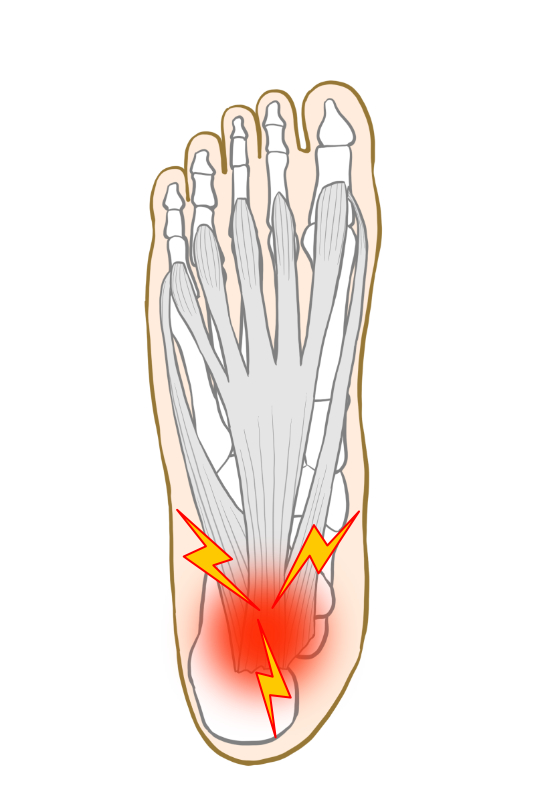

症状

荷重時の足底部痛が主な症状で、踵の腱膜起始部に最も多く発生します。特に起床時や運動開始時に強い痛みを感じる傾向があります。

- 圧痛

- 荷重時痛

- 運動開始時の痛み

- 踵骨棘形成